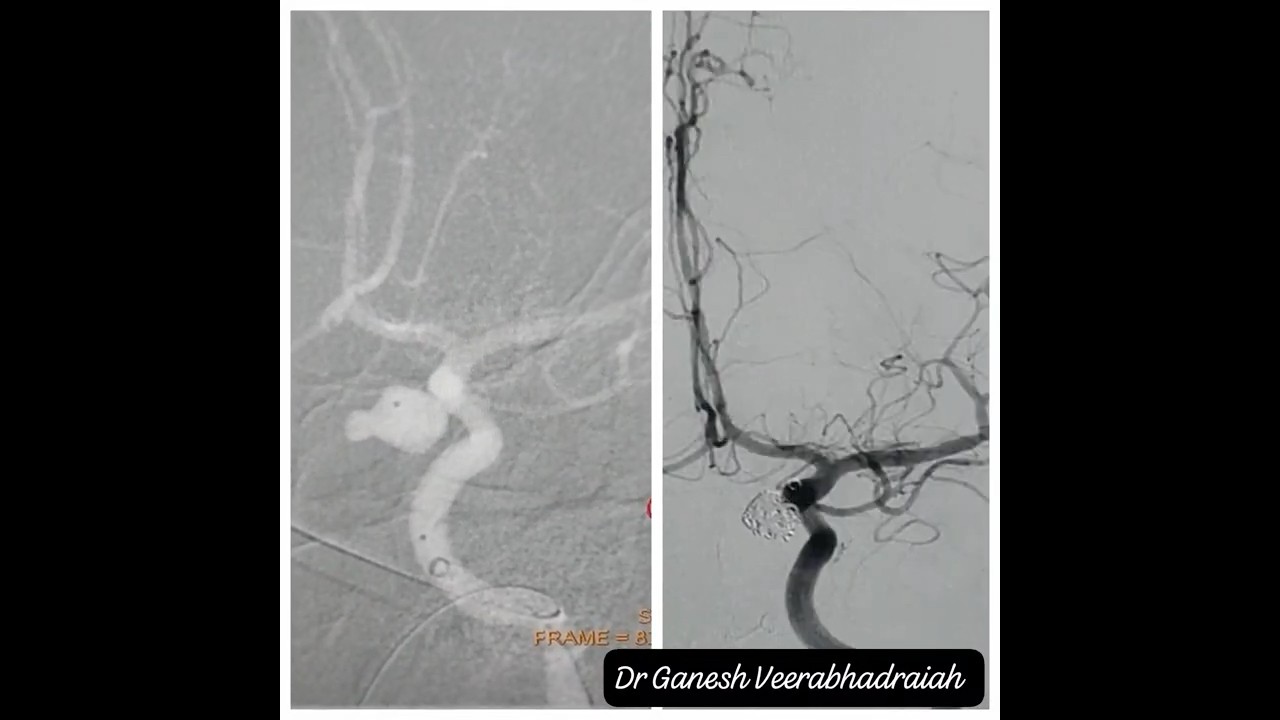

Endovascular Surgery-Coiling of Aneurysm-First coil and Complete Coiling.

Coiling is a minimally invasive procedure used to treat brain aneurysms. A thin catheter is guided into the blood vessel, and soft platinum coils are placed inside the aneurysm to block blood flow and prevent rupture. It’s a safe and effective way to reduce the risk of brain bleeding.